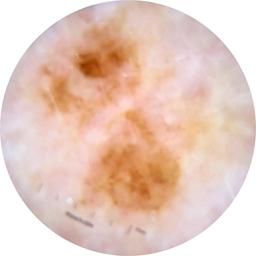

ISIC_2585736

Clinical

Field Value

acquisition_day 309

age_approx 75

anatom_site_1 Lower extremity

anatom_site_general lower extremity

concomitant_biopsy False

diagnosis_1 Benign

diagnosis_confirm_type single image expert consensus

family_hx_mm True

image_manipulation instrument only

image_type dermoscopic

lesion_id IL_4029789

patient_id IP_1553014

personal_hx_mm True

sex female